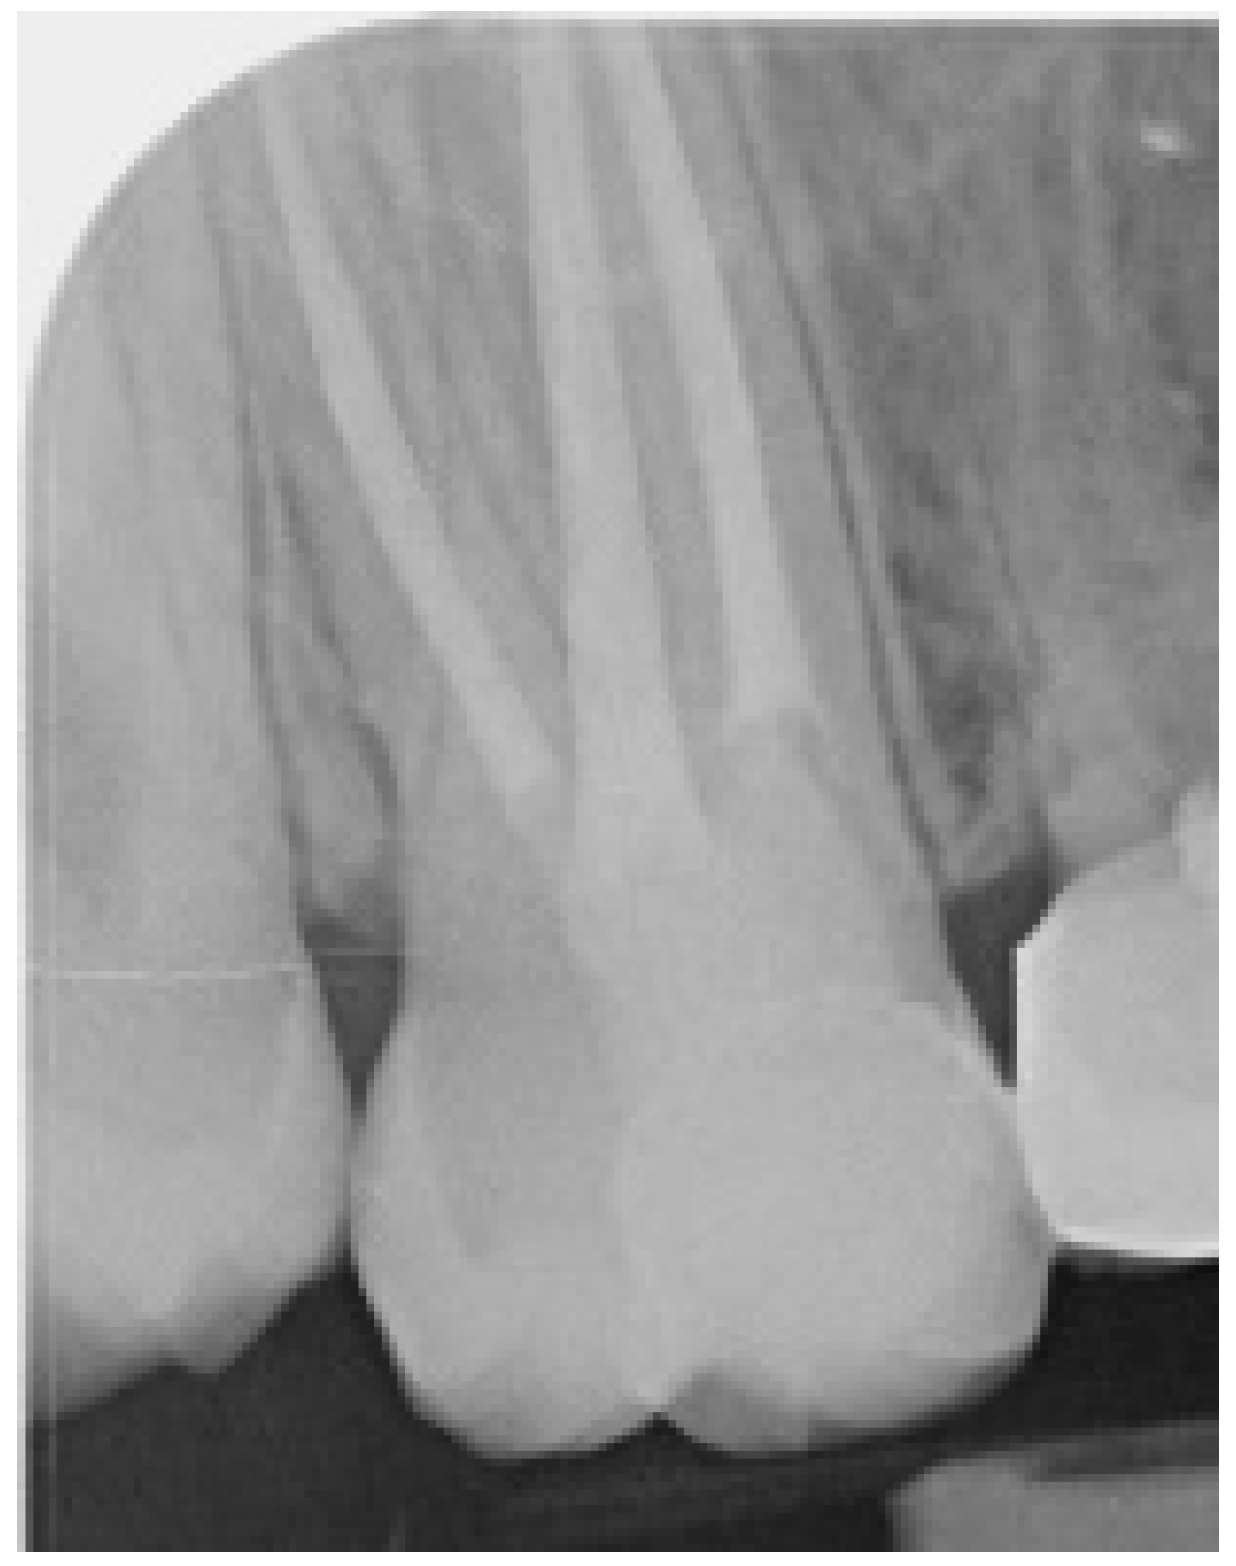

2.2. Clinical Case